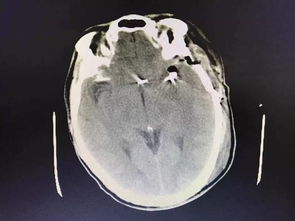

病情分析: 腦動脈血管瘤夾閉手術(shù)后偏癱失語 病情指導: 需要繼續(xù)治療,應該是傷及神經(jīng)了,腦血管瘤的治療:全切除腫瘤可治愈此病,但由于腦血管瘤的位置,瘤體的大小往往使瘤體不能完全切除,術(shù)中瘤結(jié)節(jié)的遺漏亦是腫瘤復發(fā)的一個因素。

中醫(yī)治療:服用單方含量16%以上的人參皂苷Rh2(護命素),三七,蟲草等具有抗腫瘤功效的藥物,特別是人參皂苷Rh2(護命素),是現(xiàn)代化中藥分子藥物,具有提高免疫力和抗腫瘤的雙重功效,是小分子結(jié)構(gòu),易透過人體血腦屏障,發(fā)揮功效,控制和抑制殘留腦部腫瘤細胞的生長。